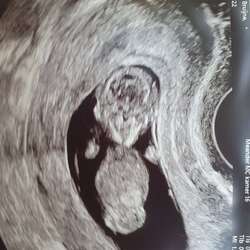

Ik heb eentje maar die is vrij duur geweest voor mijn eigen praktijk. (Vroedvrouw aan huis geweest tot 2j geleden). Ik luister om de dag eventjes en het kan absoluut geen kwaad. Ik hoor onze mini sinds 10w5d ongeveer. Toen moest ik echt duwen en achter het schaambod richten. Stilaan merk ik meer en meer naar boven te moeten zoeken (nu 14+1)

Maaaaar ik heb makkelijk praten want ik werk op radiologie en kan als ik wil zelf de echo erbij pakken. Niet helemaal subjectief dus 😉